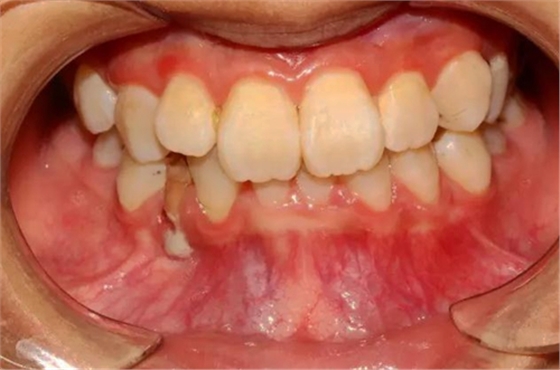

本案:患兒,女,14歲,因牙齒矯正來(lái)院,檢查見(jiàn)83滯留,43未見(jiàn)萌出,拍片發(fā)現(xiàn):43埋伏阻生于31、41、42根尖下方,按照正畸診療計(jì)劃,擬行43拔除術(shù)。

口腔牙列照片